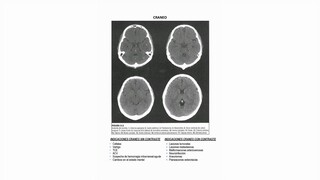

La interpretación diagnóstica de RAYOS X